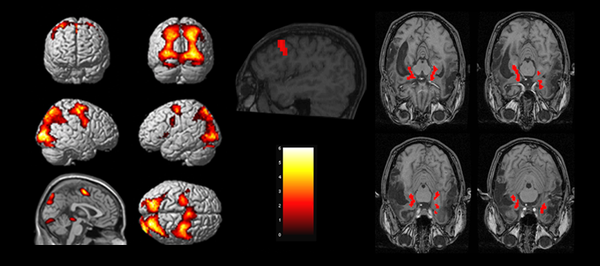

Take a look at the functional MRI images above.

Notice how different parts of the brain are firing off in each scan?

Each active part of the brain (red) was triggered when patients were asked to perform specific physical functions or recall serious traumas.